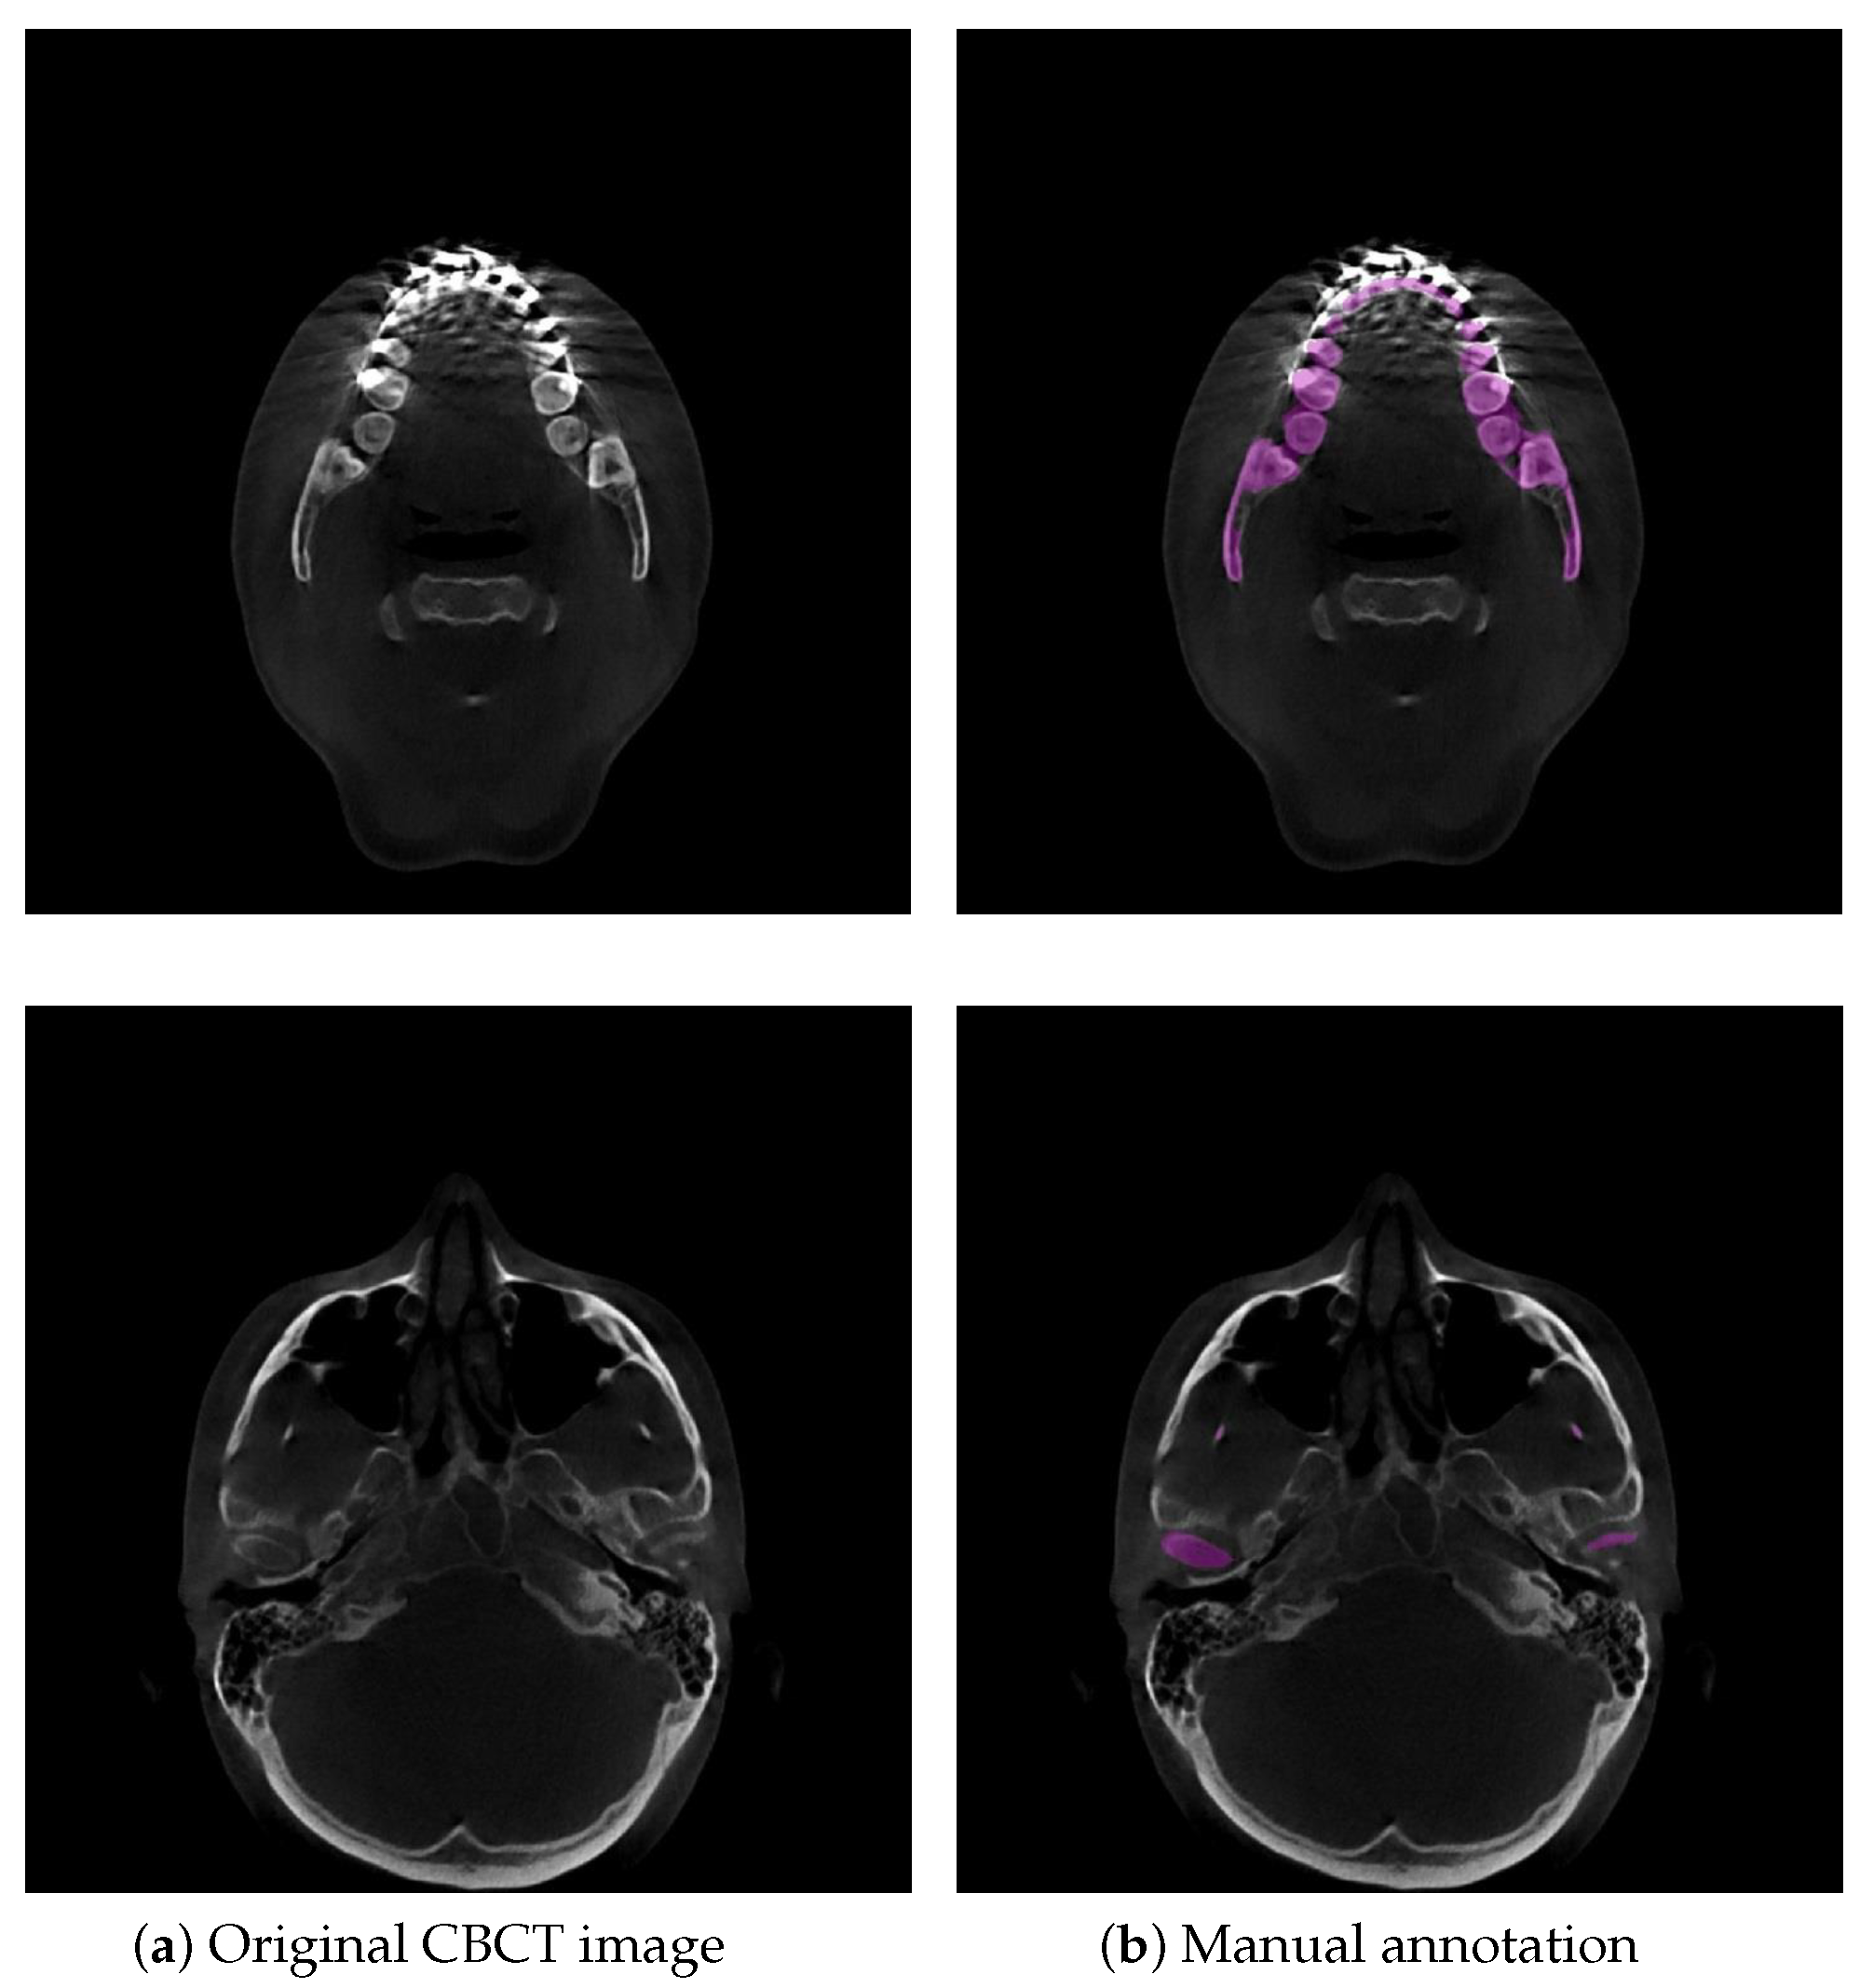

Figure 1.

Example illustrations that challenge mandible segmentation in CBCT images. (a) Original CBCT image. The mandible and teeth appear with almost invisible boundaries. (b) Example of manual annotation. Low contrast often appears in condyles. The purple region indicates the manual annotation of the mandible.

Currently, the three-dimensional (3D) virtual surgical planning (VSP) technique is commonly used for oral and maxillofacial surgery (OMFS), and planning since it allows for pre- or postoperative simulation of surgical options [1]. 3D surface models of the mandible in 3D VSP are created and superimposed to visually and quantitatively demonstrate the orthodontic/orthognathic changes and provide postoperative follow-up of patients with cranio-maxillofacial deformities [1]. Cone-beam computed tomography (CBCT) is widely applied in 3D VSP because of its lower radiation dose and faster scanning time than conventional CT [2]. In orthodontic or orthognathic treatment, the dentist or maxillofacial surgeon needs visual information about the location and movement of their patient’s teeth and mandible. A requirement for this process is to accurately segment the mandible from the dental CBCT scans and then to generate 3D surface mandible model. Therefore, accurate mandible segmentation plays an important role in 3D VSP for OMFS. Dental CBCT scans are noisier and have more metal artifacts than conventional CTs because dental CBCTs use a low-radiation technique and teeth, dental braces in orthodontic treatment and metal implants in orthognathic treatment are higher attenuation materials, easily leading to high noise and strong metal artifacts in the visual impression of the scans [3]. The boundaries of mandibles are difficult to be identified since dental braces and metal implants badly affect the image quality in CBCT [4], as shown in Figure 1. Additionally, low contrast in the condylar process very often leads to ambiguous and blurred boundaries in CBCT scans because of its low radiation dose, as illustrated in Figure 1. Consequently, the main difficulty in orthodontics or orthognathic visualization is precise mandible segmentation in CBCT scans. Currently, manual segmentation for 3D modeling of the mandible is widely adopted in clinical practice, but this is a time-consuming and labor-intensive approach so that it is impractical to perform on a large number of subjects. Moreover, manual segmentation often suffers from large interoperator variability (Dice score of between two clinical experts) [5], which directly influences the quality of treatment planning. To date, there are still no reliable automatic segmentation approaches that can adapt to badly affected CBCT scans. Accordingly, it is meaningful to develop an accurate and automatic technique to segment the mandible for orthodontic or orthognathic treatment from CBCT images.